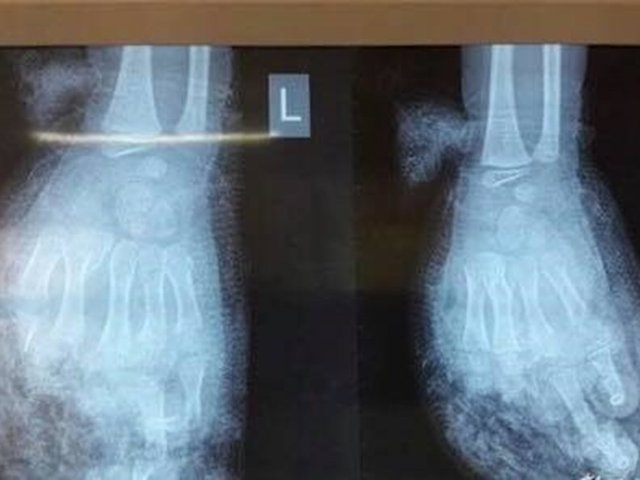

Bệnh nhi ở Nghệ An bị dập nát toàn bộ cánh tay trái, mảnh vỡ găm vào mắt.

Điện thoại phát nổ, bé 7 tuổi bị nát bàn tay

Trong lúc vừa sạc pin vừa chơi điện thoại, không may chiếc điện thoại nổ tung khiến một bé 7 tuổi ở Nghệ An bị...